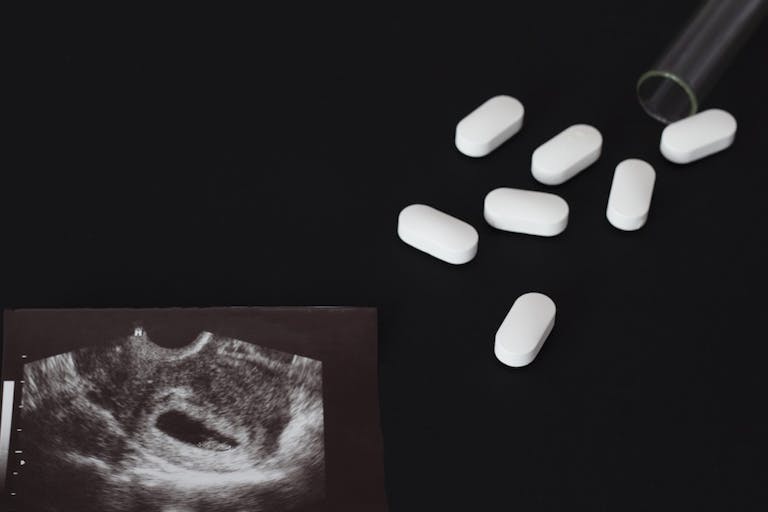

David Benjamin Coots, the married nurse who is accused of forcibly inserting abortion drugs into his girlfriend during sex, has been stripped of his nursing license by the state of Washington.

Last month, Coots was charged with second-degree assault, third-degree rape, tampering with a witness, and five counts of violation of a court order. Coots, a nurse practitioner for MultiCare, was the primary care provider of his victim, with whom he allegedly persistently pursued a relationship after she became his patient in January of 2023. After he told her he was getting a divorce, they began a relationship in September of 2023. In January of 2024, the victim learned she was pregnant, and though she said Coots originally acted “overly supportive,” he allegedly had other intentions.

The victim claimed he first tried to force her to drink a coffee, which she thinks was drugged; then, she noted that he was “abnormally aggressive” during sex, and was doing things he “has never done before.” He also tried to prevent her from using the bathroom afterward, but when she did, she found a pill on her toilet paper, and then later, found a second pill along with “some kind of foil.” Though Coots initially denied it when she confronted him, she said he eventually admitted to inserting four abortion-inducing pills inside her body during sex. He then gave her a $2,000 check in an effort to keep her from going to the police. She refused the money.